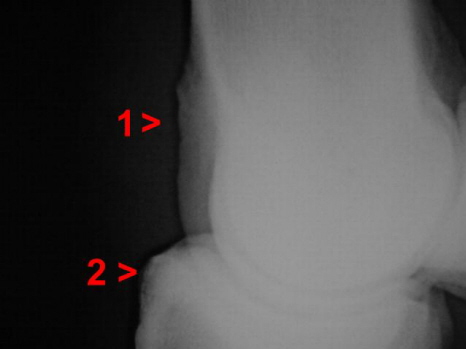

Arthrose Fesselgelenk